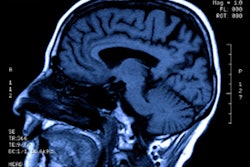

Patient 102 had bilateral but asymmetrical hyperintensities in the temporal lobes seen on fluid-attenuated inversion recovery (FLAIR) images and diffusion-weighted imaging (DWI) magnetic resonance imaging sequences. Patient 16 had right thalamic hypersignal on FLAIR and DWI sequences (arrowheads), ipsilateral to the insular lesion. Patient 79 had extensive brain lesions, showing bilateral temporal, frontal, and insular signal abnormalities. ADC indicates apparent diffusion coefficient; T1W, T1-weighted. Image and caption courtesy of JAMA Network Open.Sarton's team found that, at 90 days post-ICU admission, 95 patients (68.8%) had a poor outcome, including 16 deaths (11.6%). The group also found that there were particular factors associated with these outcomes.